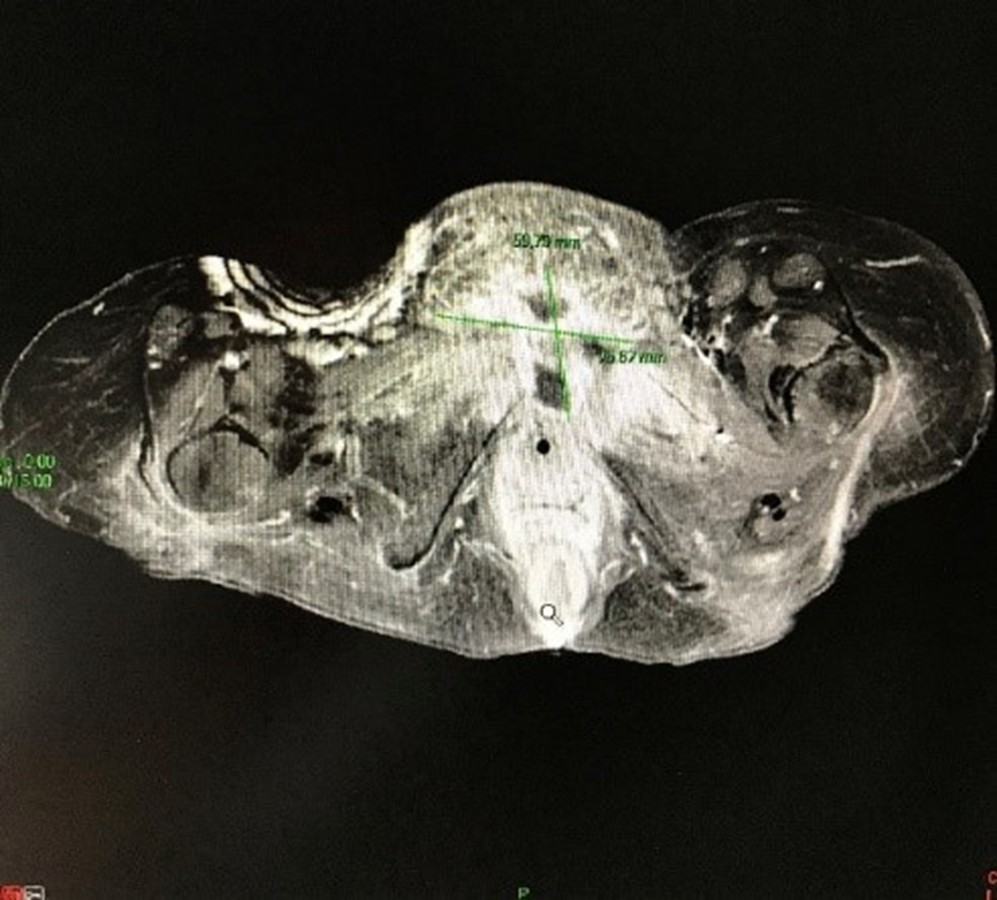

The MRI scan showed a parasymphyseal collection associated with pubic osteitis and bone lysis (Figure 1). The collection was aspirated and the fluid analyzed. Cultures obtained from the parasymphyseal collection grew Bacteroides fragilis (4+) and Peptostreptococcus anaerobius under anaerobic conditions.

Based on MRI findings, positive cultures, and systemic inflammatory markers, we concluded that autonomic dysreflexia was triggered by septic symphysitis with adjacent osteomyelitis, associated with a parasymphyseal collection and bone lysis.

Figure 1. MRI scan shows the presence of a parasymphyseal collection surrounding pubic osteitis with bone lysis.